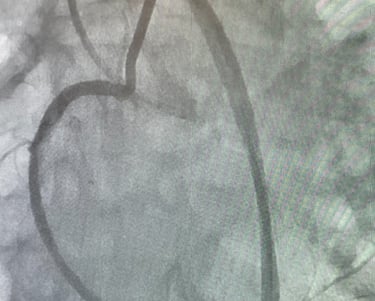

La cardiologie interventionnelle est une profession médicale passionnante. Son objectif principal est de repousser les limites de la cardiologie en utilisant des techniques avancées pour traiter les maladies cardiaques. Grâce à notre passion pour la recherche, nous sommes constamment à l’affut de nouvelles découvertes et de nouvelles technologies pour améliorer les soins aux patients.